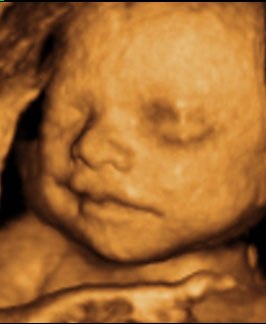

Kan da lige sætte et par billeder ind fra i mandags, hvor jeg var 27+5 uger henne, så du kan se kvaliteten

Vedhæftede fotos (klik for at se i fuld størrelse)